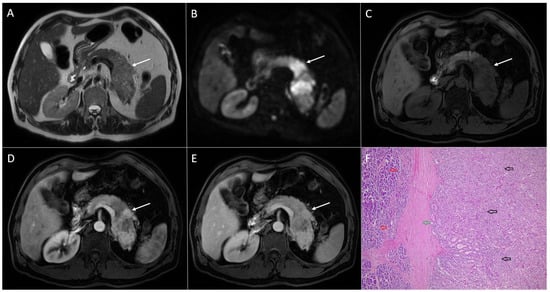

3.4. Pancreatic Metastases